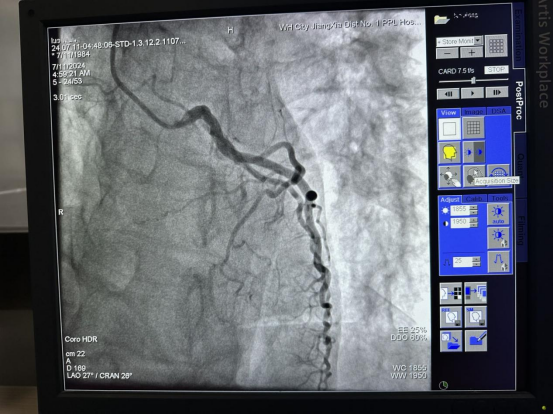

“情况比想象的更严重!”据张凯主任医师介绍,入院1小时后,患者在全麻状态下行气管插管接有创呼吸机呼吸支持,完善冠脉造影检查提示,其冠状动脉前降支近段发出第一对角支后完全闭塞。面对这一紧急情况,手术团队迅速而冷静地制定了周密的手术方案,并全神贯注地投入到这场与时间的竞速中。

“从入院到血管再通,串联植入支架,不足90分钟。”随着导丝小心翼翼地穿越闭塞段,手术进入了最为关键的阶段。在影像引导下,手术团队精准操作、密切配合,成功穿越了闭塞的血管段,为后续的治疗打开了通路。紧接着,两枚支架被依次植入患者前降支中段至近段,它们像桥梁一样稳固地支撑起狭窄的血管壁,彻底打通了堵塞的血管,恢复了心脏血流供应。